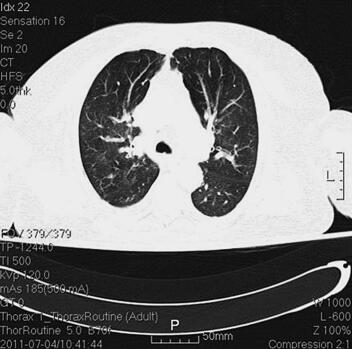

体格检查:P 85次/分,R 12次/分(机械通气),BP 121/61mmHg(多巴胺针剂维持下),T 37.3℃,SPO2 98%。神志清,精神差,气管居中,口插管在位,机械通气,颈静脉无怒张,桶状胸,两肺呼吸音粗,可闻及大量湿啰音及干啰音,心率85次/分,窦性,律齐,双下肢无明显水肿。辅助检查:胸部CT(6月28日)(图1):两肺感染性病变,两下肺支气管扩张症伴感染。心电图(6月28日):窦性心律,T波改变。血常规(6月28日):WBC 13.5×109/L,N 66.3%,Hb 145g/L;CRP(6月28日)3.8mg/L,PCT(6月28日)5.49ng/ml。

图1 胸部CT(6月28日):两肺感染性病变,两下肺支气管扩张症伴感染